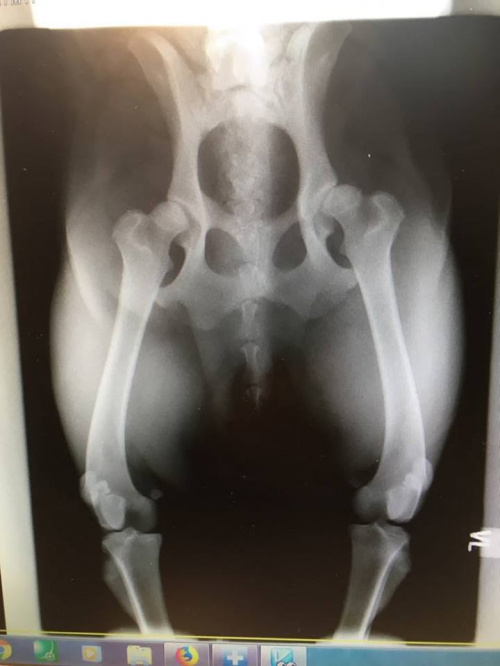

U nas trochę nowości ! Blues starszy Golden zaniemógł fizycznie z powodu bólu stawów łokciowych - RTG potwierdziło straszne zwyrodnienia, miał blokade dostawową , jest lepiej, zastanawiam sie nad wprowadzeniem oleju z marihuany , czytałam na forum , zę działa cuda. A Lampo też miał wykonane RTG i okazało się , że ma dysplazję stawów biodrowych , lewego bardziej :-/ na razie brak wskazań do jakiejś chirurgicznej interwencji, mamy być pod kontrolą RTG i ma mieć leki suplementujące, ale jeszcze ich nie mamy. I ograniczenie ruchu, co w jego przypadku będzie najgorsze, na dworze szaleje z piłką i Bluesem! Macie jakieś pomysły jak jeszcze można pomóc?

Hej, my tez wiele dobrego czytaliśmy o olejku, zaczęliśmy go stosować bo Binek również ma problemy z chodzeniem. Na pewno może pomoc a nie zaszkodzi. Wiele psow postawił na nogi. Ale przykra wiadomość jeśli chodzi o młodego Lampo! Dacie radę wrzucić tu zdjęcie Rtg? Jak bardzo silna jest ta dysplazja? Czy Widać po nim ze my doskwiera ból? :(

Jeszcze nie mam RTG dopiero odbiorę od weterynarza i postaram sie wrzucić, wet mówił, zę na razie nie jest dysplazja mocno zaawansowana, po Lampo nie widać żadnych objawów, ja zrobiłam RTG profilaktycznie, bo jest psem energicznym i rozbrykanym i kocha biegać , no ale trudno, trochę ograniczymy zabawy z piłką, ale do końca na pewno nie !

Nareszcie mam RTG Lampo ! Samopoczucie świetne, olej stosujemy i suplement na stawy. Nazwa mi umknęła. Myślę, że będzie dobrze !